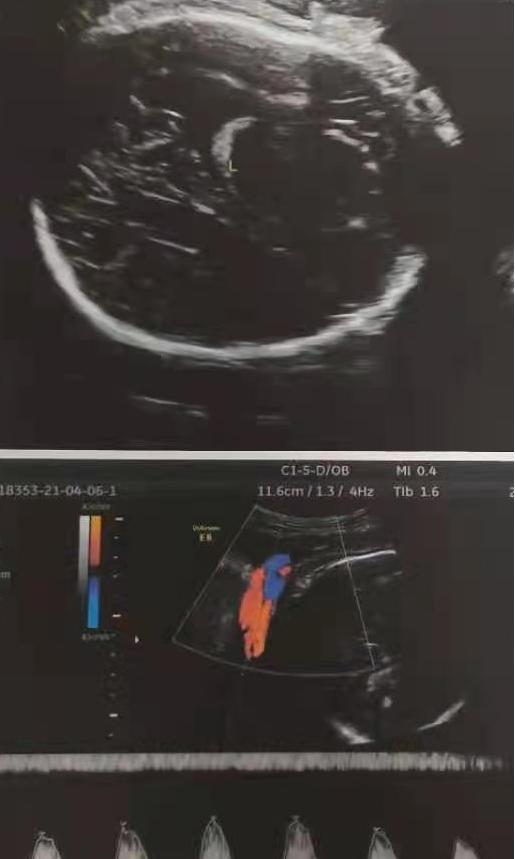

结合病史及查体情况,初步考虑诊断:1.脐带绕颈3周2.G1P0 38+6周孕待产,遂建议孕妇办理入院,进行住院治疗。入院后,患者完善了彩超检查,结果提示:胎先露:头;胎盘位置:宮体前壁。成熟度3级,胎盘厚度36mm,下缘距宫颈内口尚远。胎心率131bpm,律齐。胎儿左侧侧脑室后角因位于近场显示欠清,宽约10.6mm。

再次告知了孕妇及其家属麻醉风险及剖宫产过程中的风险后,孕妇及家属仍然选择进行剖宫产,于是我为患者完善了相关的术前检查,包括血常规、尿常规、肝肾功能、凝血象、血糖、B超等,并严密监测血压、胎心、胎动及产兆。术前相关检查结果回示正常后,为患者在硬膜外麻醉下行了子宫下段横切口剖宫产手术,手术过程顺利,成功娩出一活女婴。术后诊断:1.脐带绕颈3周 2.G1P1 38+6周孕剖宫产已产。

在硬膜外麻醉下为孕妇进行了子宫下段横切口剖宫产手术,术中见:子宫如孕周大小,子宫下段形成7cm,形成可,刺破羊膜囊,见羊水0°,约550ml,吸尽羊水后顺利娩出一活女婴,Apgar评分9(肤色-1)-10-10分,新生儿外观无畸形,体重5000g,脐带长约90cm。